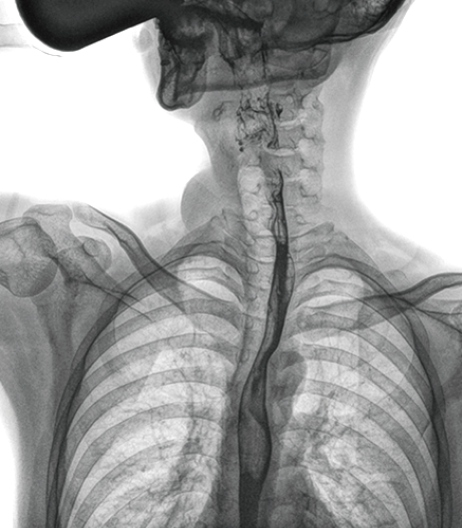

食管造影是食管病變的基本檢查方法,可以發現食管癌的特征性改變——食管粘膜的中斷和破壞,病人常感覺吞咽障礙,此特征在臨床中最常見,也是早期食管癌的典型表現。一般伴隨的特征有管壁充盈缺損、龕影、軟組織塊影、食管腔狹窄等;在透視下還可看到食管壁僵硬、蠕動緩慢等。

在食管造影檢查中,由于吞咽鋇劑后,造影劑流速非常快,動態DR影像采集幅面大,普利德多功能動態DR 17×17英寸超大視野,一次曝光即可顯示整個食管,更方便觀察食管的病變,確定病變的范圍,對診斷和治療有重要參考價值。

動態 DR 可以動態觀察管壁蠕動是否僵硬,以鑒別良、惡性狹窄,不但在透視過程中,可實時高清點片,實現毫秒級動靜態圖像切換,快速捕捉病變部位的影像,成像清晰而迅速,盡可能減少食管功能性障礙患者因吞咽困難而忍受痛苦的時間,同時提高醫生做出正確診斷的效率,還能實時保存視頻影像,反復觀察、分析,明確病變范圍,對手術有重要的指導意義。

與過去的數字胃腸機比較,動態DR圖像分辨率高,對食管的全景觀察,局部粘膜破壞、中斷,管腔狹窄以及病灶范圍的顯示清晰度明顯更優。

上消化道造影高清圖像

由此不難看出,動態DR在食管造影的臨床應用上,相比于其他檢查手段,成像清晰、應用便捷,而且能夠充分顯示食管的局部和整體結構形態,并以此揭示相關形態和功能性改變,更有利于助力實現精準診斷。